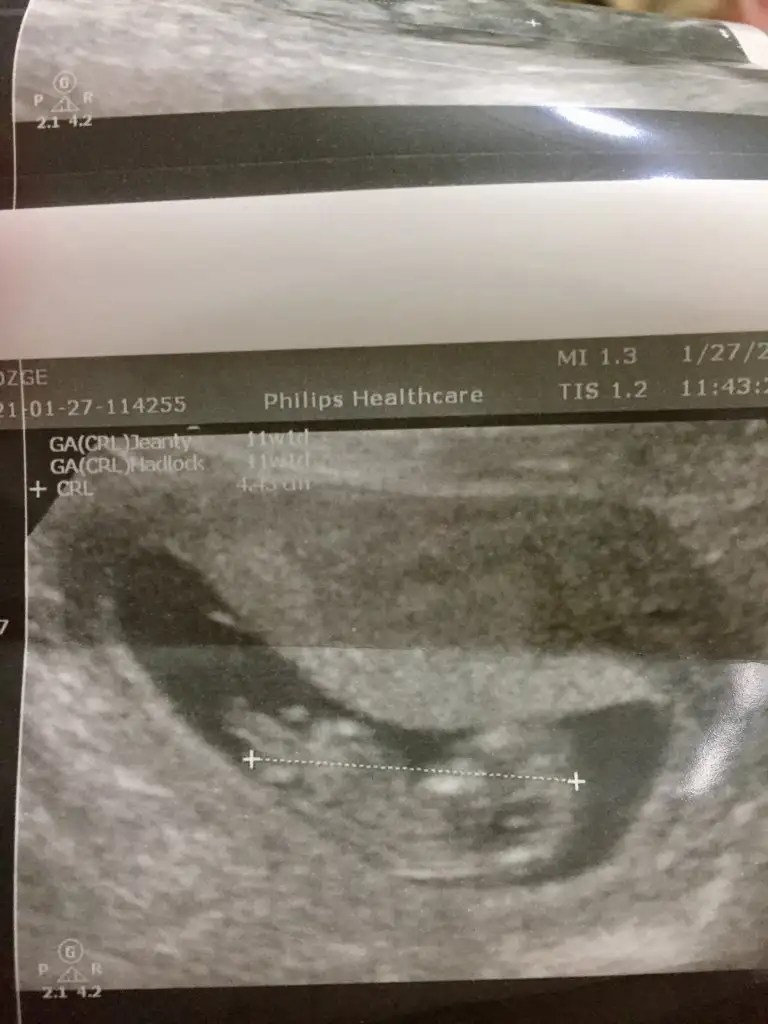

Merhaba Ikra meyra Ikra meyra rica etsem bana da bi tahmin de bulunabilir misin 🙏🏻😊11+11

• 54B101D6-D23C-441C-BC00-CC8CF32314D4.webp

54B101D6-D23C-441C-BC00-CC8CF32314D4.webp

29,7 KB · Görüntüleme: 50

• 39CF7A4C-8688-496F-8924-527F43B5EFCD.webp

39CF7A4C-8688-496F-8924-527F43B5EFCD.webp

31,3 KB · Görüntüleme: 54

• 60B99C41-D4F2-4F76-8F85-184DC7F50134.webp

60B99C41-D4F2-4F76-8F85-184DC7F50134.webp

31,8 KB · Görüntüleme: 46